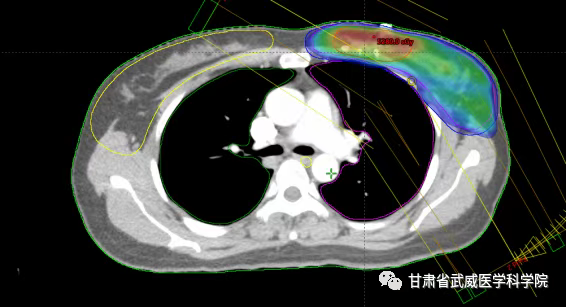

SIB-VMAT放疗计划

我院放疗五科胡廷朝副主任医师近几年开展了保乳术后的大分割放疗,目前已治疗病例20余例,瘤床给予39.5Gy,全乳43.5Gy采用VMAT同步推量技术,将之前的30次放疗时间缩短到15次,3周完成治疗,减少住院时间,几乎无严重并发症的发生,提高了患者术后放疗的依从性,节省了患者的治疗费用,受到了广大患者的好评及认可。此项技术的开展,为广大乳腺癌患者节省了治疗费用,带来了实惠,随着大分割放疗技术应用范围进一步得到拓展,未来预计越来越多的患者会从大分割全乳放疗中获益。使放射治疗进入一个更为“轻松”的时代。